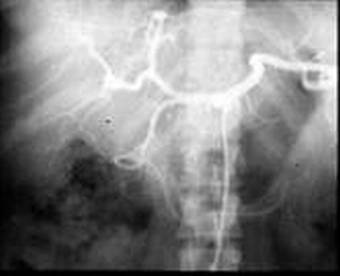

n вирсунготомия эндоскопическая, операционная (редкоприменяемое вмешательство, вследствие технической сложности и редкости стеноза вирсунгова протока изолированно в его устье), ЭПСТ

n панкреатоеюностомия:

а) продольная (Пестова-Джильсби)

б) терминальная (Дюваля)

n ОККЛЮЗИЯ ПРОТОКОВ PANCREAS; ЭНДОСКОПИЧЕСКАЯ ОПЕРАЦИОННАЯ (РЕТРОГРАДНАЯ И АНТЕГРАДНАЯ)